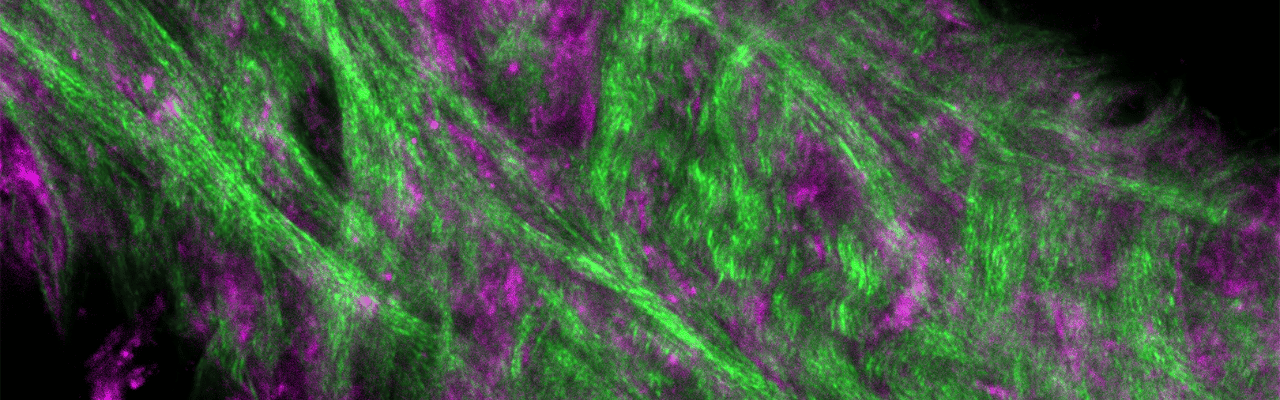

Study Sheds Light on Cloudiness After Corneal Cross-Linking

Keratoconus is a condition where the cornea, the clear front surface of the eye, gradually thins and bulges outward, distorting vision. This condition affects both eyes and impacts about 1 in 2,000 people. It is not caused by inflammation, and it can severely impair vision. One treatment for keratoconus is corneal cross-linking (CXL), a procedure designed to strengthen the cornea by making it more rigid, preventing further deterioration. While effective in halting the progression of the condition, CXL has some challenges. The procedure can cause cell death in the treated area, and patients often develop a cloudy region in the cornea, called haze, which can persist. In a recent study led by Matthew Petroll, Ph.D., Professor of Ophthalmology and Biomedical Engineering, advanced imaging techniques were used to investigate why this haze develops. The study found that after CXL, cells in the cornea, which usually move freely between collagen layers, become restricted. Instead, they cluster and move together as groups, leading to uneven healing. This irregular healing pattern scatters light in the cornea, resulting in the cloudy appearance that affects vision. The Petroll Lab is now focused on understanding how CXL alters the physical properties of the cornea and how these changes influence cell behavior and healing. Their goal is to improve the treatment, promoting better healing and clearer vision for patients with keratoconus.